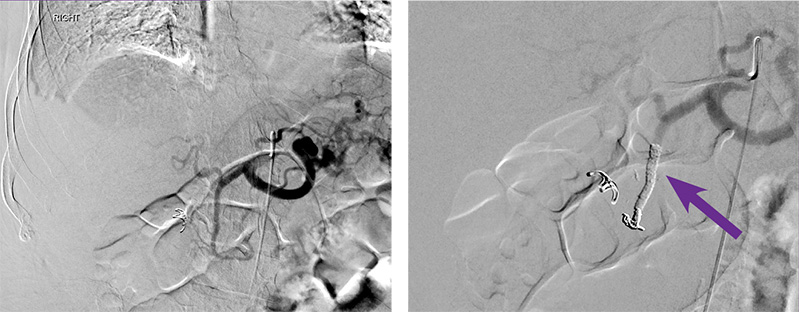

Gastroduodenal artery (GDA) embolization

Courtesy of Dr. Gary Siskin I Albany Medical Center

73-year-old male patient with a PMH significant for CKD, HTN, and lumbar spine surgery who presents with acute GI bleeding. Endoscopy demonstrated one non-bleeding ulcer in the duodenal bulb and a second slowly bleeding ulcer in the second portion of the duodenum that was treated with an epinephrine injection and placement of a hemostatic clip due to continued bleeding, endoscopy was repeated, demonstrating spurting blood from the previously treated ulcer which was treated again with an epinephrine injection and fulguration. Angiography was then performed.

Intervention used

Arterial access was gained via the right common femoral artery. A Sos-2 catheter was positioned at the origin of the celiac axis and an angiogram was performed, which failed to demonstrate any abnormalities of the gastroduodenal artery (GDA). This was confirmed after selective catheterization and angiography of the GDA with a Renegade™ HI-FLO™ Microcatheter. Prophylactic embolization of the GDA was then performed with two 4 mm X 15 cm Embold™ Detachable Coils followed by administration of 0.5 mL of Obsidio Embolic (purple arrow). Follow-up angiography demonstrated successful occlusion of the GDA.

Following embolization, he received 1u of additional PRBCs and his hemoglobin subsequently remained stable. He was discharged with a hemoglobin of 8.7 g/dL.